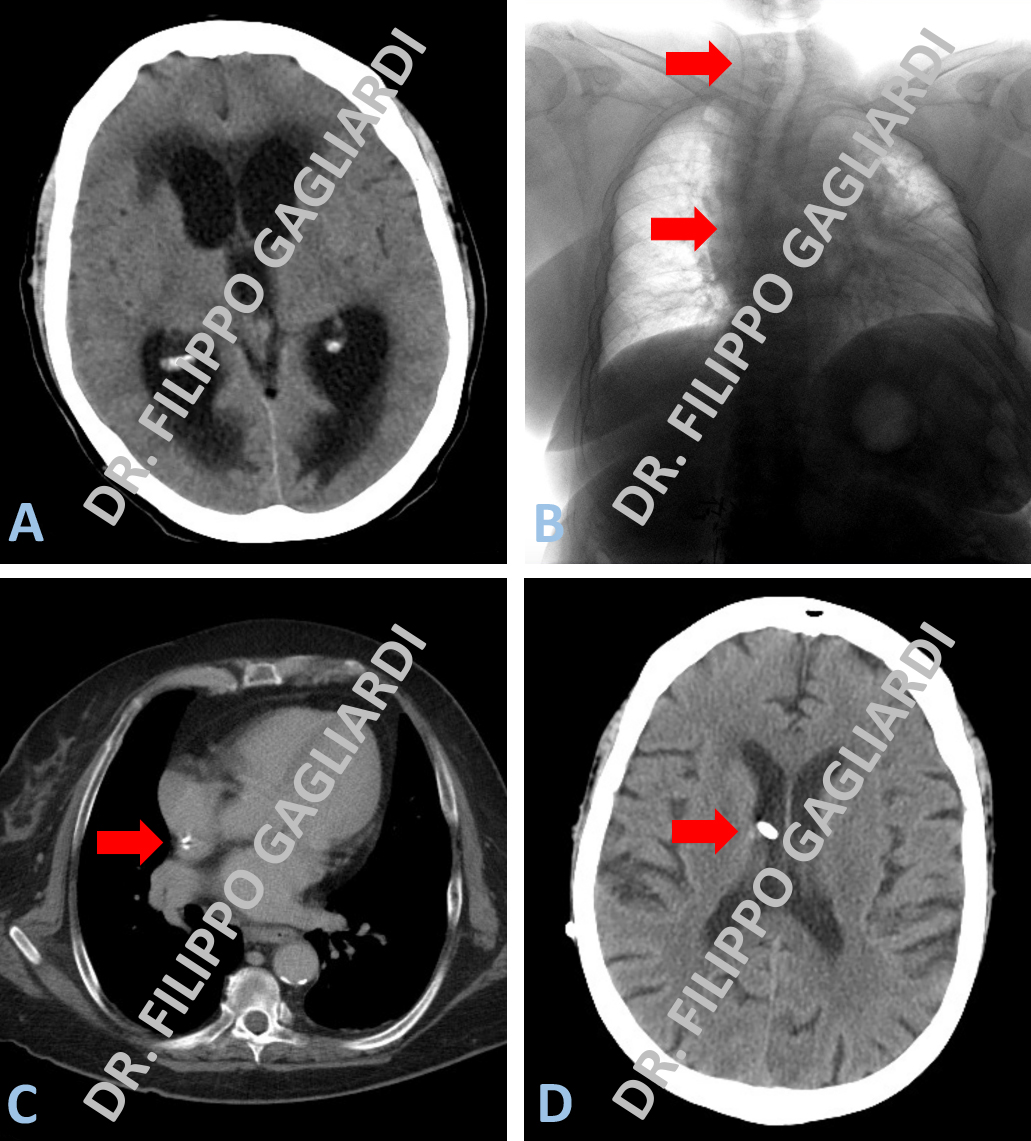

Idrocefalo trattato con derivazione ventricolo-atriale

Esempio di derivazione ventricolare in caso di idrocefalo iperteso (dilatazione dei ventricoli cerebrali) condizionante un quadro di ipertensione intra-cranica. I ventricoli, gli spazi neri che si apprezzano all’interno del cranio alla TC pre-operatoria, risultano dilatati. L’alone grigio scuro che li contorna rappresenta la trasudazione del liquido in essi contenuto nel tessuto cerebrale circostante, dovuto all’elevata pressione del sistema (figura A). Il Paziente è stato sottoposto ad un intervento di derivazione ventricolo-atriale, ovvero al posizionamento di uno shunt (drenaggio) che dalle cavità ventricolari, passando nel sottocute della testa e del collo, attraverso la vena giugulare, raggiunge l’atrio destro del cuore dove scarica nel circolo sanguigno l’eccesso di liquido cefalo-rachidiano. La figura B mostra la lastra del torace dove si può apprezzare il decorso del catetere. La figura C mostra l’estremo del catetere, posizionato nel cuore, alla TC torace di controllo post-operatorio; la figura C documenta invece il controllo TC encefalo dopo l’intervento, dove si può notare il ridimensionamento delle cavità ventricolari con la completa risoluzione del quadro di idrocefalo.